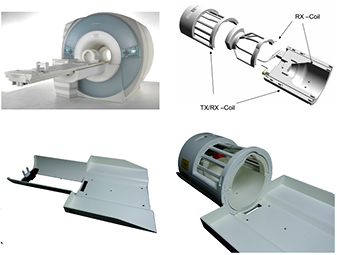

Based on the work of Rothfuss et al we developed an AC method using 176Lu background radiation for the MR compatible BrainPET insert for a clinical 3T magnetom Trio MR produced by Siemens Healthcare GmbH (figure 2, left). The insert consists of 32 copper shielded detector cassettes with an inner diameter of 36 cm and 19.2 cm axial FOV. Each cassette contains 6 scintillation detector blocks built with 12 × 12 LSO crystals of 2.5 mm pitch in both directions and 20 mm length. Since the natural background activity from 176Lu is 255  in LSO, the total natural activity in the scintillator of the MR-BrainPET is 881 kBq. This activity is much lower than the activity of transmission sources used in PET scanners with an integrated transmission source and is far too low for generating low noise AC maps for the Tx/Rx coil, that are of sufficient quality, by simultaneous acquisition transmission and emission data during a human study. Moreover, a simultaneous acquisition would require high resolution time of flight (TOF) measurements, Mollet et al (2014) which are not possible with the BrainPET insert due to the relatively low timing resolution of the avalanche photo diods (APDs). However, the same Tx/Rx head coil will be used for all measurements with the 3T MR-BrainPET. It is attached to the patient bed (see figure 2) and always positioned at the same location within the FOV. Thus, making it possible to acquire the transmission data of the bed and the Tx/Rx head coil without the subject and over a much longer measurement time than the relatively short times required for human studies. While Rothfuss et al proposed a maximum likelihood expectation maximisation algorithm for reconstructing the attenuation map from an object scan and a blank scan, we computed the ACF values as defined in equation (4). The BrainPET FOV is too small for reconstructing an attenuation map from the transmission acquisition because only coincidences between one cassette and its 19 opposed cassettes are registered. It is not possible to change the configuration for accepting coincidences between the PET cassettes and, as a result, this leads to missing projections for the reconstruction of the Tx/Rx head coil attenuation map, as shown by the red sectors in figure 3.

in LSO, the total natural activity in the scintillator of the MR-BrainPET is 881 kBq. This activity is much lower than the activity of transmission sources used in PET scanners with an integrated transmission source and is far too low for generating low noise AC maps for the Tx/Rx coil, that are of sufficient quality, by simultaneous acquisition transmission and emission data during a human study. Moreover, a simultaneous acquisition would require high resolution time of flight (TOF) measurements, Mollet et al (2014) which are not possible with the BrainPET insert due to the relatively low timing resolution of the avalanche photo diods (APDs). However, the same Tx/Rx head coil will be used for all measurements with the 3T MR-BrainPET. It is attached to the patient bed (see figure 2) and always positioned at the same location within the FOV. Thus, making it possible to acquire the transmission data of the bed and the Tx/Rx head coil without the subject and over a much longer measurement time than the relatively short times required for human studies. While Rothfuss et al proposed a maximum likelihood expectation maximisation algorithm for reconstructing the attenuation map from an object scan and a blank scan, we computed the ACF values as defined in equation (4). The BrainPET FOV is too small for reconstructing an attenuation map from the transmission acquisition because only coincidences between one cassette and its 19 opposed cassettes are registered. It is not possible to change the configuration for accepting coincidences between the PET cassettes and, as a result, this leads to missing projections for the reconstruction of the Tx/Rx head coil attenuation map, as shown by the red sectors in figure 3.

Figure 2. Upper left: Siemens Trio 3T MRT with BrainPET insert and dedicated head Tx/Rx coil. Upper right: detailed view of the Tx/Rx head coil. Lower left: head coil holding extension for the patient bed of the Siemens Trio 3T MRT with BrainPET insert. Lower right: head coil holding extension together with Tx/Rx coil.